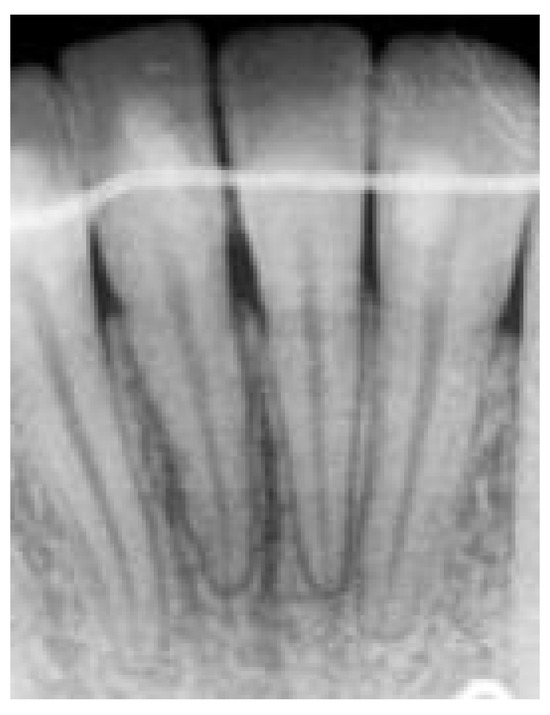

Long cône / endodontie / implantologie

Le long cone dentaire est un examen radiographique intra-oral permettant l’analyse détaillée d’une dent et de ses structures de soutien.